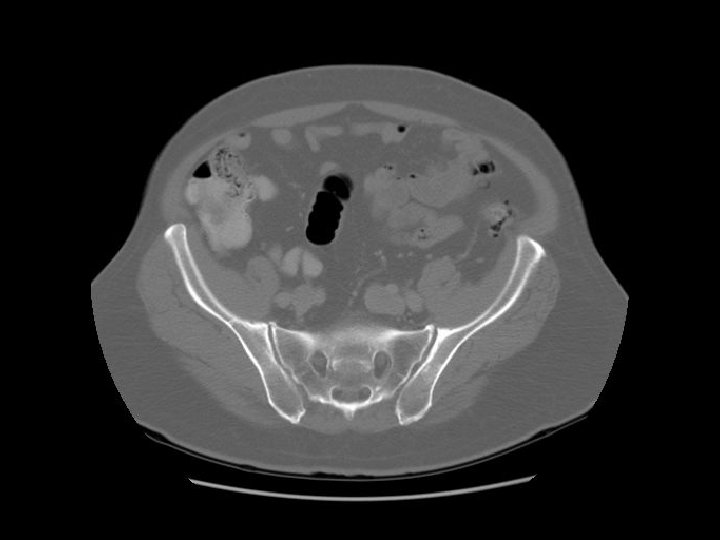

Rt common iliac artery IVC Lt common iliac artery

L 5

Arrows are pointing to the common iliac veins joining to form the IVC. Left

Ilium Sacrum

Arrows are pointing to the internal and external iliac veins joining to form the common iliac vein.

Rectosigmoid Sacroiliac joint